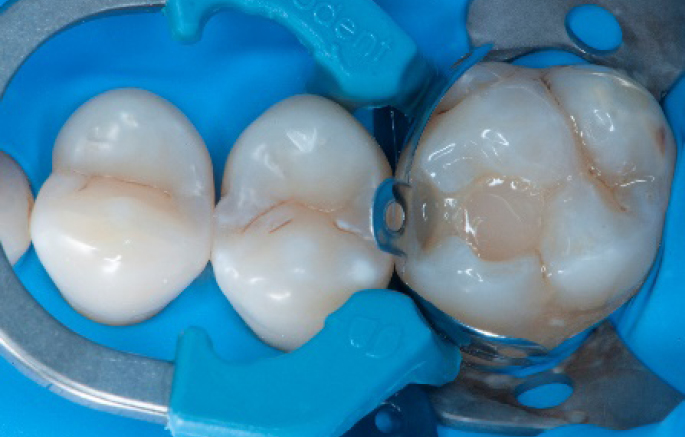

Step 1:

The situation after rubber dam isolation.

Step 4:

The complete Palodent1 system in place: sectional matrix, wedge and ring.